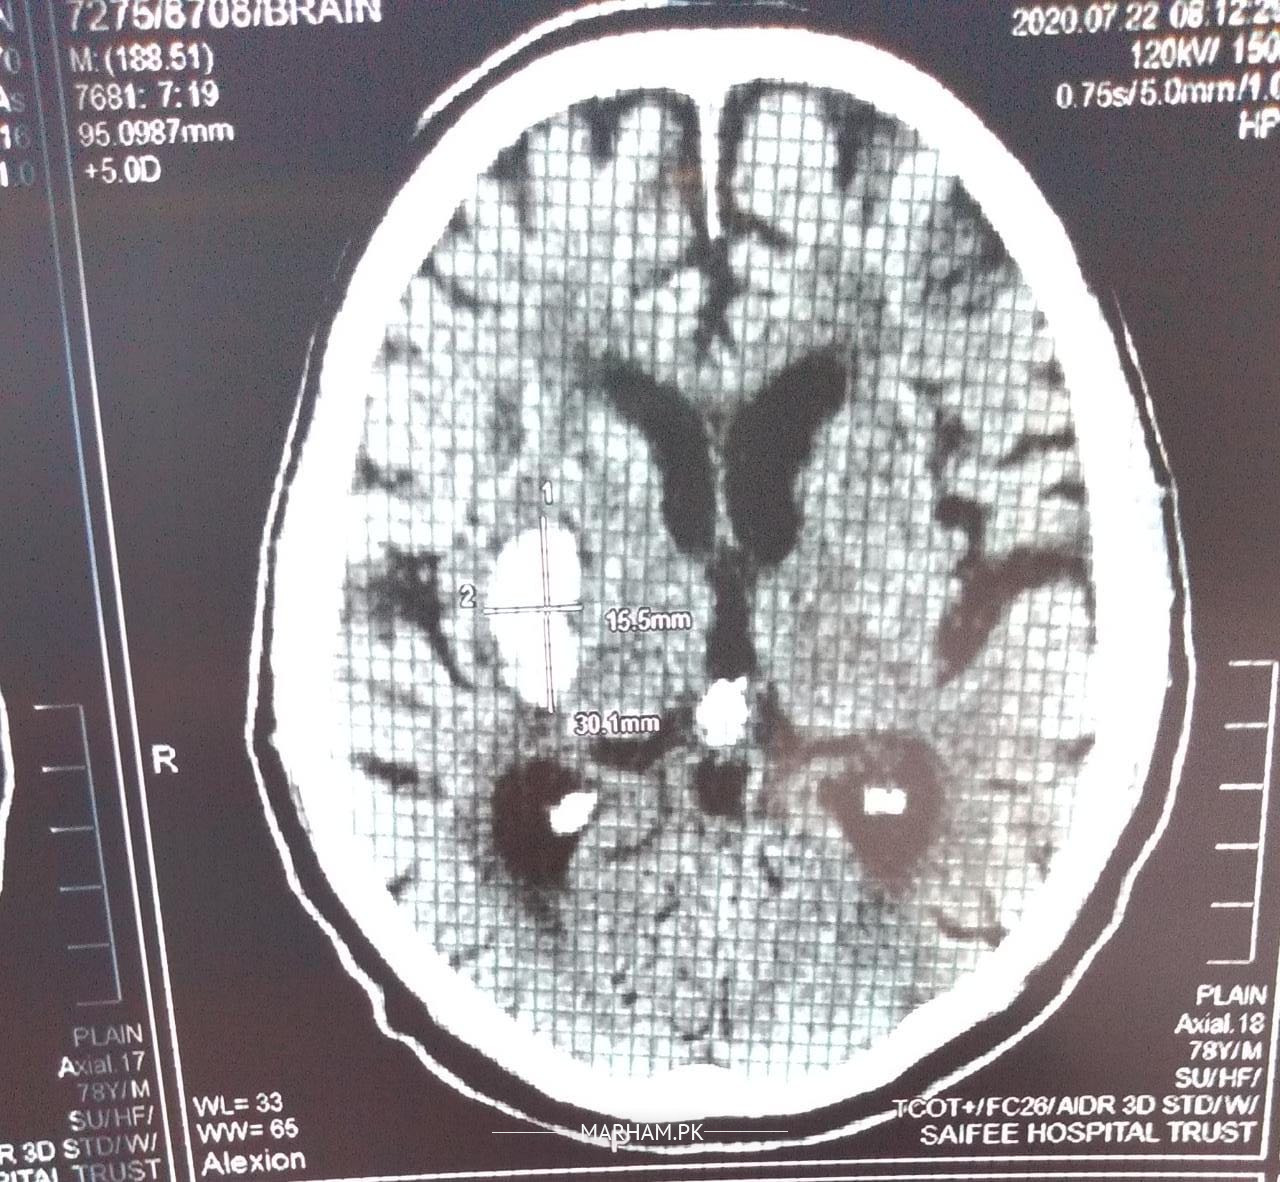

My father is severely depressed due to covid going on from past few months, lost interest in everything he would like to do earlier. He is a cardiac patient and had his cardiac bypass in 1995. He was very active entire life and never smoked or drank. Now from past few months he has stopped going out and 3/4 days ago he has stopped moving hisself from bed and says his left arm and leg is numb, we took him to hospital and got it checked his ECG, blood pressure and everything else was normal but in CT scan they found a white spot (attachment below) on right side of brain. He does feel his legs and arm now after 3rd he has stared moving his arm himself but complain pain in his left foot. In hospital they said it’s not stroke as they did come check up but they wanted to keep him in hospital for observation but they had only space in covid ward so they said we gonna put him on suspected covid patient my brother refused and brought him home. He is better but we are not sure what has happene

Also Sharing saifiee hospital report please check

Sorry for a late reply as i couldn’t receive ur msg due to some technical problems in the website. Hope your father is doing well. Well, according to the report there’s a possibility of stroke (falaj), and for further evaluation you may book an online appointment so that a detailed history can be taken and then medication can be given.

Saifiee report